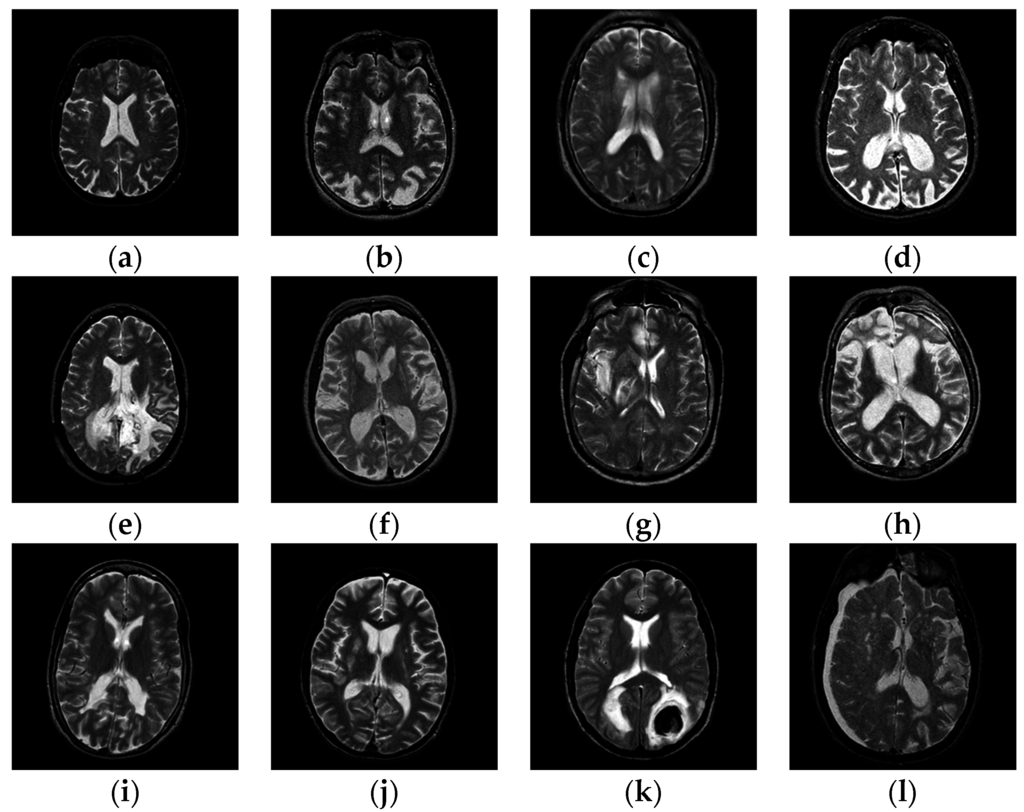

3. Materials

At present, there are three benchmark datasets of different sizes, viz., D66, D160, and D255. They were all used for our tests. All datasets contain T2-weighted MR brain images, which were acquired along the axial axis with sizes of 256 × 256. The readers can download them from the Medical School of Harvard University website. The first two datasets consisted of examples from seven types of diseases (meningioma, AD, AD plus visual agnosia, Huntington’s disease, sarcoma, Pick’s disease, and glioma) along with normal brain images. The last dataset D255 contains all seven types of diseases as mentioned before, and four new diseases (multiple sclerosis, cerebral toxoplasmosis, chronic subdural hematoma, and herpes encephalitis). Figure 1 shows samples of the brain images.

Figure 1. Samples of pathological brain images: (a) healthy brain; (b) AD with visual agnosia; (c) Meningioma; (d) AD; (e) Glioma; (f) Huntington’s disease; (g) Herpes encephalitis; (h) Pick’s disease; (i) Multiple sclerosis; (j) Cerebral toxoplasmosis; (k) Sarcoma; (l) Subdural hematoma.